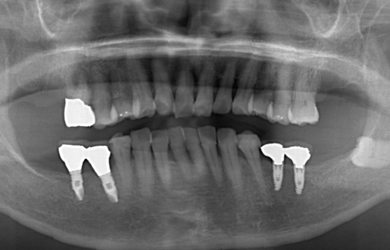

インプラントの症例写真 IMPLANT

スピードインプラント治療+セラミック治療

| 治療方針 | 抜歯と同時にインプラント治療を行うことにより、治療期間を短縮。 | ||||||||||||||||||||||||||||||||

| 治療内容 | インプラント4本(通常インプラント3本、抜歯即日スピードインプラント1本)、ハイブリッドセラミック5本 | ||||||||||||||||||||||||||||||||

| 総治療費 | 1,385,800円 | ||||||||||||||||||||||||||||||||

| 治療期間 | 4ヵ月+6ヶ月 |